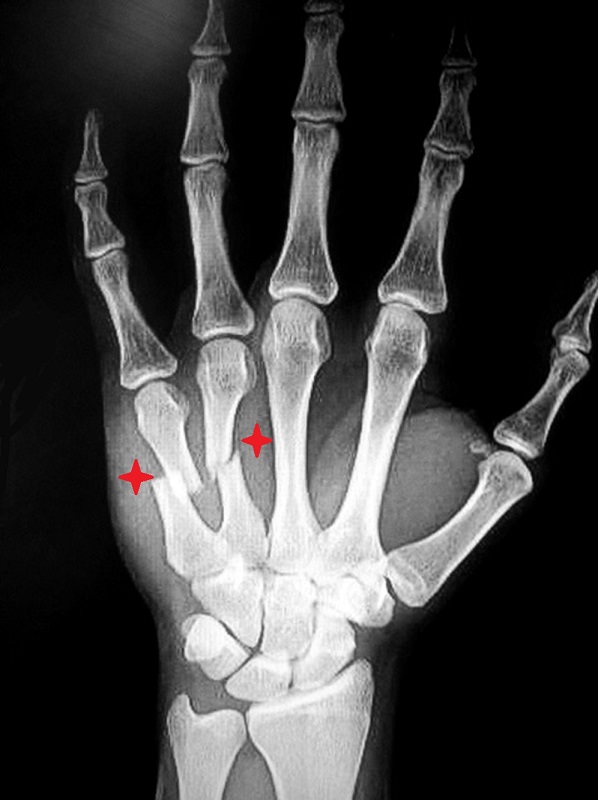

3-3: علائم وتشخیص شکستگی متاکارپ های کف دست: بدنبال شکستگی پشت دست متورم و دردناک شده و فشار به محل شکسته شده شدت درد را افزایش میدهد. پوست روی استخوان شکسته ممکن است کبود شود. مشت کردن دست معمولا شدت درد را افزایش میدهد. تشخیص این شکستگی ها با رادیوگرافی ساده است.

3-4 : درمان شکستگی های متاکارپ: در شکستگی های بدون جابجایی یا با جابجایی اندک، تنها درمان مورد نیاز استفاده از یک آتل برای بیحرکت کردن محل شکستگی و کاهش درد است. در مواردیکه جابجایی قطعات شکسته شده زیاد باشد درمان بصورت جااندازی بسته و گچ گیری است. در مواردی که شکستگی بعد از جااندازی ناپایدار باشد پزشک معالج با استفاده از پین های فلزی که آنها را از طریق پوست به داخل استخوان و محل شکستگی هدایت میکند، قطعات شکسته شده را به یکدیگر متصل میکند. در مواردی که جااندازی بسته موفقیت آمیز نباشد پزشک معالج اقدام به جااندازی باز شکستگی و فیکس کردن قطعات شکسته شده بوسیله پین یا پیچ و پلاک میکند.